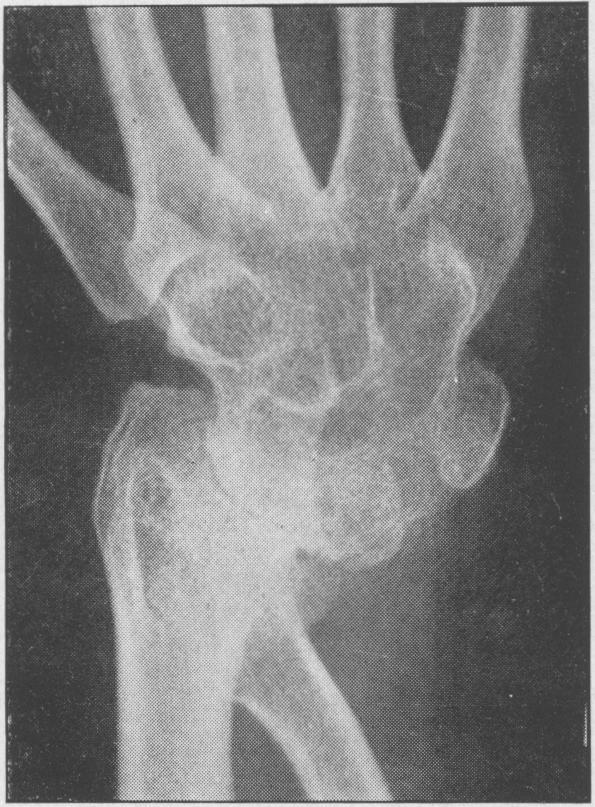

Juvenile rheumatoid arthritis (Still's disease).